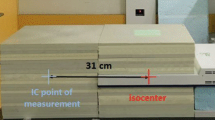

In addition, patients treated with PBI at the CTL received a daily CBCT, which might also contribute to increase the risk of RISM. We therefore simulated the dose deposited in patients by a daily CBCT using an in-house developed method based on Monte Carlo calculations. Briefly, a BEAMnrc [29] model of the CBCT, calibrated to absolute dose for the respective CBCT protocol, was applied on the patient’s planning CT. The resulting dose distribution was then summed with the patient’s treatment plan for total dose distribution. We incorporated these values into our model for risk estimation generating cumulative DVHs considering 15 CBCTs. Patients treated with WBI at the CTL did not receive a homogeneous number of CBCT, following our institutional standard of a daily CBCT during the first 3 fractions and subsequently a patient-adapted CBCT frequency according to individual positioning reproducibility. Therefore, we did not consider the additional CBCT dose (highly variable from patient to patient, according to CBCTs number) for the projected risk of RISM for WBI patients. Nonetheless, we reported the impact of exemplarily 6 CBCT (according to our clinical practice, where patients receive at least 3 CBCTs the first week, 2 the second week, 1 the last week) on the mean dose of the different organs at risk (OARs).